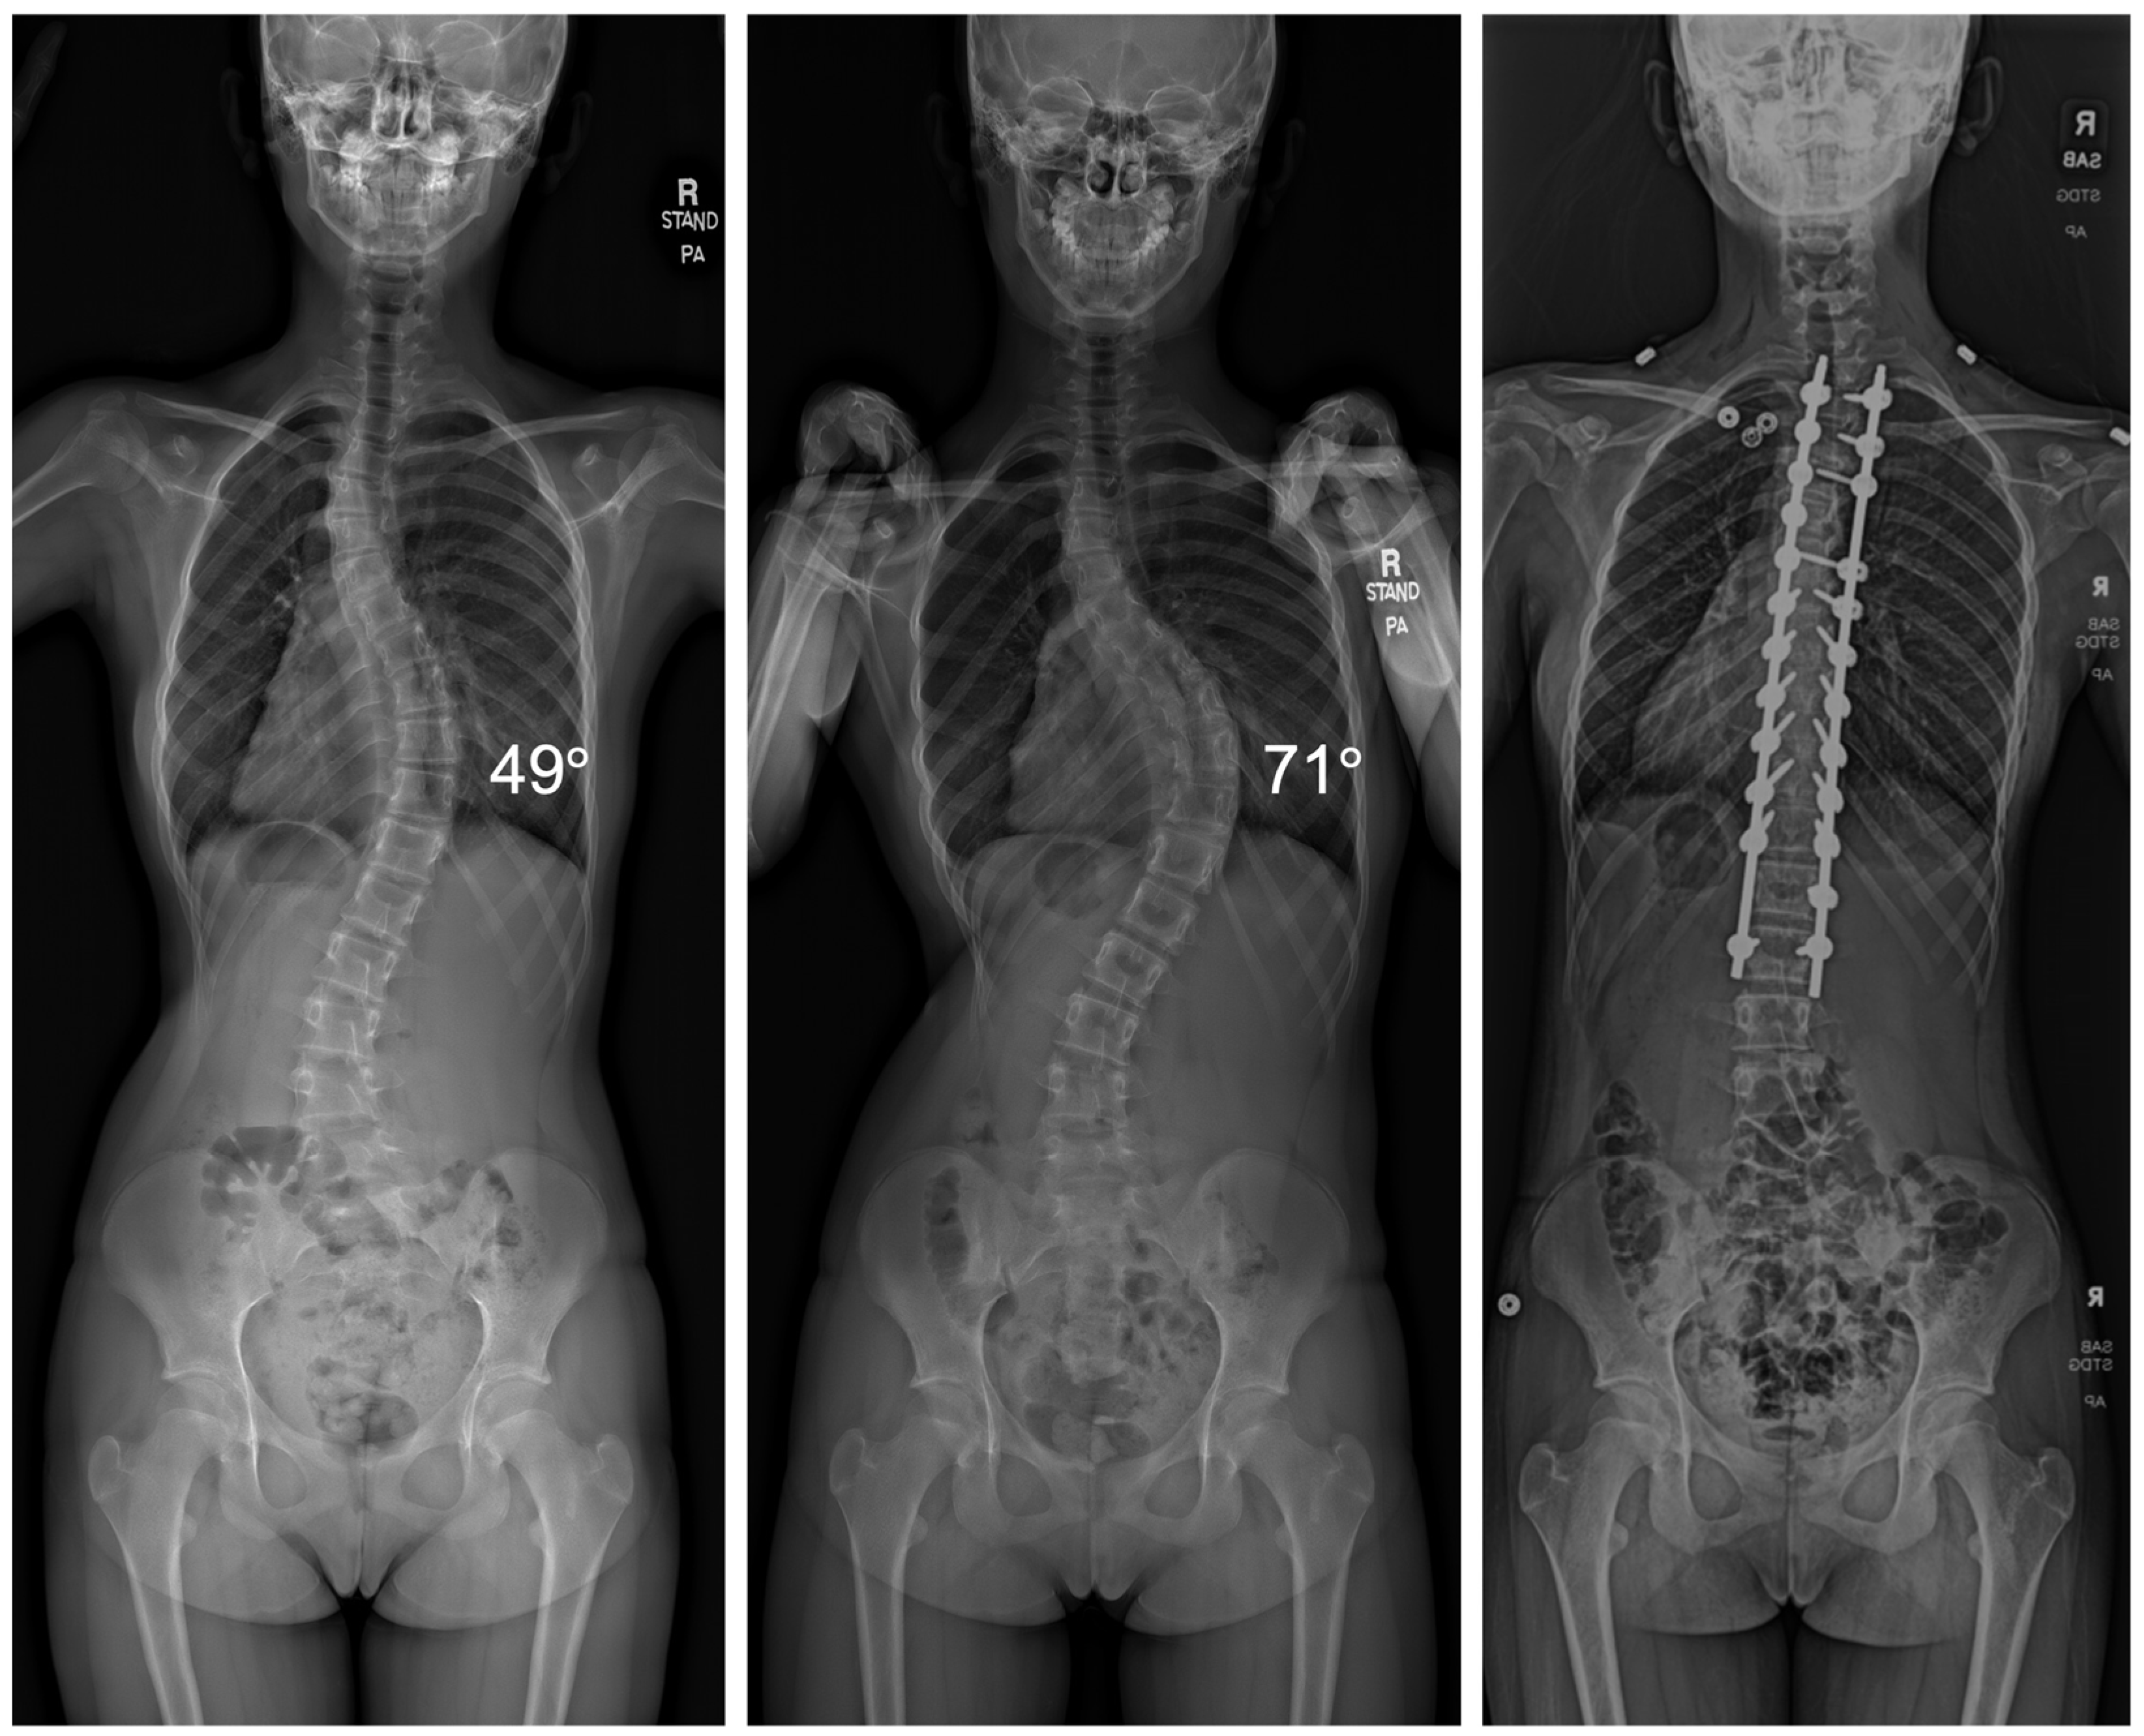

Among the 95 patients treated, there was an average curve progression of 5.2 degrees while awaiting surgery. This equated to an average of 1.91 degrees per month. A total of 48 patients of the 95 experienced curve progression of ≥5 degrees. Of the 91 patients that underwent VBT, 66 received thoracic tethers (72.5%), 12 received lumbar tethers (13.2%), and 13 received both thoracic and lumbar tethers (14.3%). Three patients required thoracic PSF, and one patient underwent both thoracic and lumbar PSF (Figure 1).

Figure 1.

Radiographic imaging of a patient before and after a 6-month surgical delay that resulted in curve progression from 49° to 71°, requiring the transition from VBT to PSF.

Patients with VBT with thoracic tethers had an average progression of 4.5 degrees (range: −7 degrees to 32 degrees), while patients with lumbar tethers had an average progression of 2.8 degrees (range: −6 degrees to 12 degrees). Patients with both thoracic and lumbar tethers had an average thoracic progression of 6.2 degrees (range: 2 degrees to 22 degrees) and an average lumbar progression of 5.2 degrees (range: −1 degrees to 21 degrees). Patients that required PSF had an average thoracic progression of 14 degrees (range: 6 degrees to 21 degrees). The single patient with a lumbar curve had a progression of 13 degrees.